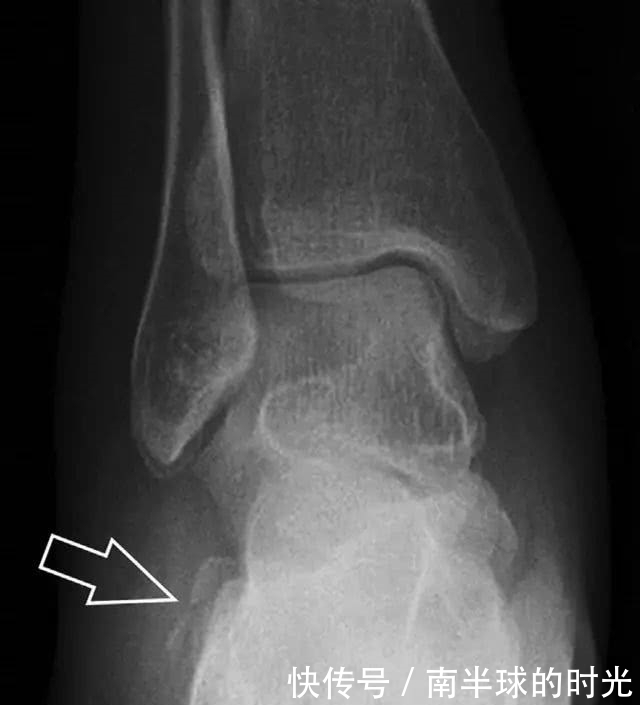

跟骨前突骨折

呈 Y 形的分歧韧带附着于跟骨前突上,是维持踝关节跖屈和背屈稳定性的重要结构。跟骨前突骨折常发生于足跖屈内旋、分歧韧带被牵拉时,或者足背屈外旋、骰骨和距骨挤压前突时。而这些骨折在初次 X 线检查时常常被漏诊掉。踝部侧位片诊断这些骨折最佳,准确诊断的关键点在于,必须仔细查看是否存在骨皮质中断(图 6)。如果侧位片可疑,建议加做斜位片协助诊断。

图 6 跟骨前突骨折。A 侧位片示跟骨前突骨折(箭头),与舟骨的重叠使骨折显示模糊;B 另一位患者的侧位片示内翻损伤所致的骨折(箭头),这种损伤机制引起小块的骨折